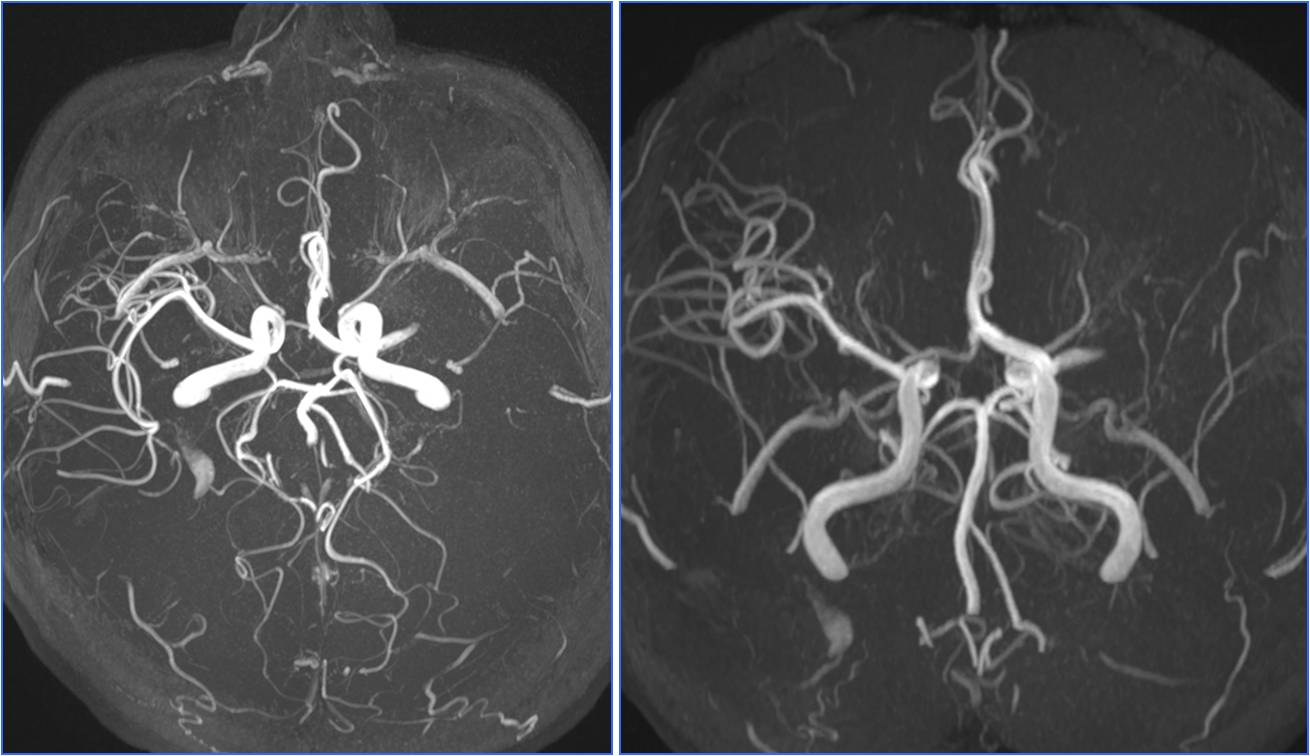

▼术前头MRA

▼术后24小时CT

》查找病因

》TCD发泡试验提示右向左固有型大分流

》经食道超声提示房间隔缺损大小约8mm

》转心外科行微创房间隔缺损封堵术

▼术后24小时头MRA

》肥胖,长期坐位工作

》颈动脉超声、心脏超声未见异常

》胸部CT未见异常

》血糖、血脂、同型半胱氨酸正常

》TCD发泡试验提示右向左潜在型小分流